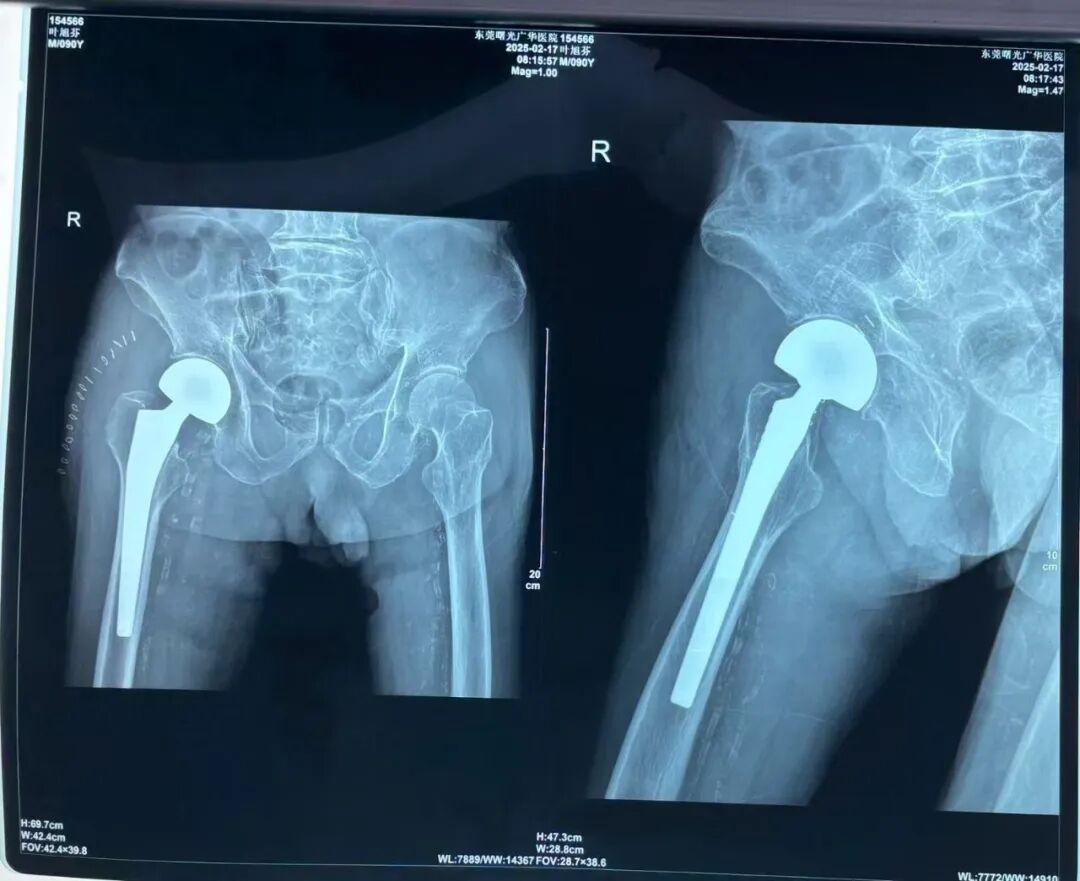

95岁的患者叶老先生,因不慎跌倒导致右股骨颈骨折,同时伴有肺支气管扩张感染、白内障、脑萎缩等十余项基础疾病,身体状况极为复杂。面对高龄患者的治疗风险,我院外一科(骨科)迅速启动多学科协作机制,联合麻醉科、呼吸内科、心血管科等专家团队进行术前综合评估,制定个性化手术方案。在严密控制基础疾病后,团队凭借丰富的经验和精湛的技术,成功为患者实施右侧髋关节置换术,手术全程仅耗时1小时,术中出血量低至100ml,最大程度降低了对患者身体的负担。

骨科团队为患者实施右侧髋关节置换术